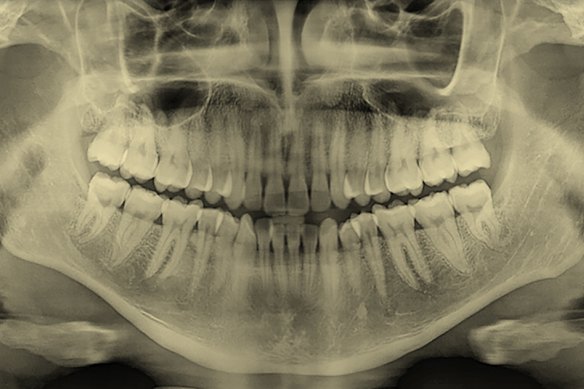

The roots of teeth extend into the upper and lower jawbones, as in this X-ray of adult teeth.

‘A prevailing fixation’: Why do we love straight, white teeth?

Teeth are essential to everyday life – and they carry our secrets long after we’re gone. What do they know? (And what makes a “perfect” smile?)